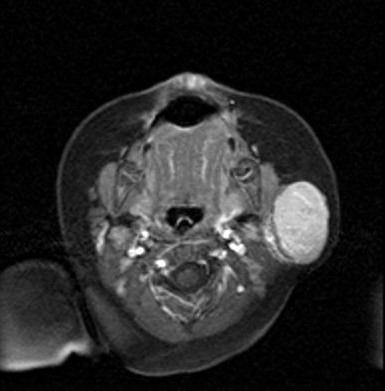

Hemangioma infantil en la glándula parótida. Aportación de dos nuevos casos

Cristina Muñoz López, Julia Pareja Grande, Eva Sauces Martínez, Laura Acero García de la Santa, Miguel Ángel García Cabezas, Fernando Dotor García Soto

32-35